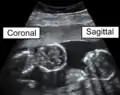

The sagittal plane (/ˈsæɪtəl/; also known as the longitudinal plane) is an anatomical plane that divides the body into right and left sections.[1] It is perpendicular to the transverse and coronal planes. The plane may be in the center of the body and divide it into two equal parts (mid-sagittal), or away from the midline and divide it into unequal parts (para-sagittal).

The main anatomical planes of the human body, including mid-sagittal or median (red), parasagittal (yellow), frontal or coronal plane (blue) and transverse or axial plane (green)